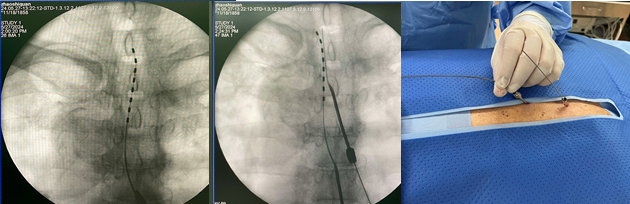

首场专题讲座,张毅博士介绍脊髓电刺激(spinal cord stimulation, SCS)的理论基础和实践应用。SCS是给疼痛患者硬膜外腔植入外科或穿刺电极,通过特定频率和脉宽电流,刺激支配疼痛区域相应脊髓节段而产生麻刺感,从而获得镇痛效果的一种神经调控疗法。SCS能够降低神经病理性疼痛患者的疼痛评分,并明显改善睡眠状况、运动功能和生活质量。适用证包括:带状疱疹后神经痛(PHN)、糖尿病周围神经性疼痛(PDPN)、腰椎手术失败综合征(FBSS)、复杂区域疼痛综合征(CRPS)、慢性神经根病相关疼痛等。张博士通过13个临床案例分享其在脊髓电刺激的手术操作技巧和围术期管理经验。

脊髓电刺激(SCS)植入术的示意图

脊髓电刺激植入术技巧展示